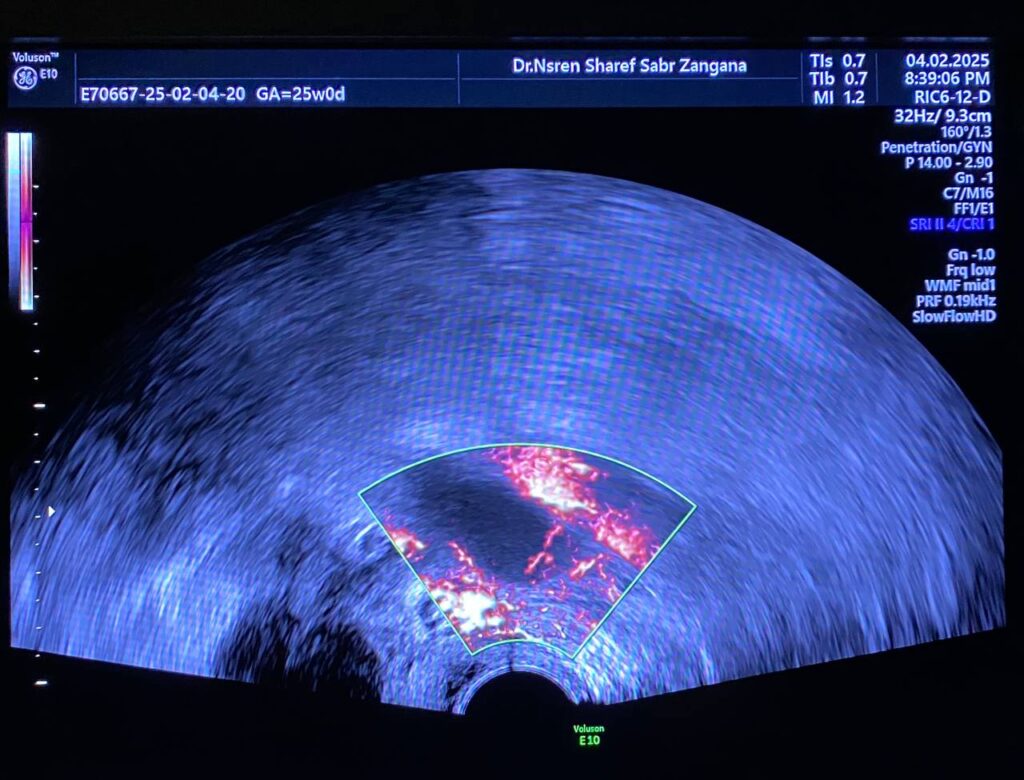

Bulky uterus, endometrial lining thickness 2mm, occupied by clear avascular fluid , mostly due to mass effect , Presence of hypoechoic solid mass 68x48mm ,vascular on color Doppler , Color Score 4 (Hyper vascular) , within right sided posterior submucosal subserosal region , associated with other two smaller masses seen on the anterior wall , their sizes are 19x18mm& 8x12mm (Metastasis? Lymphoma ??) or other suspicious masses